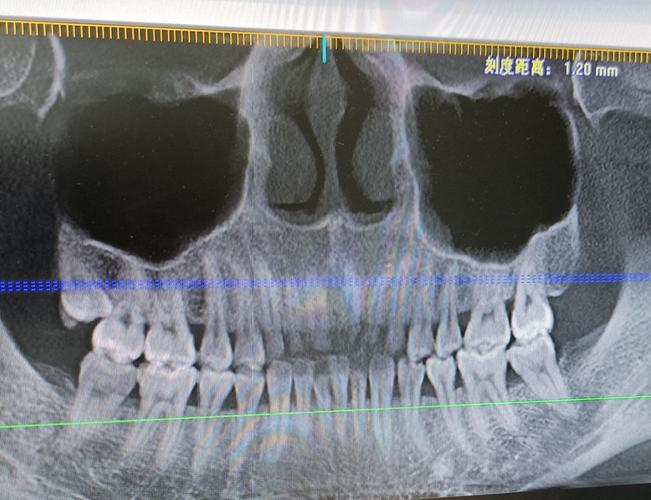

第一次拍牙片,医生说我牙根挺长的,嘿嘿. 牙周不好,哎

分享一下我的牙片 以及上面的智齿需要拔吗

5岁小孩的牙片!

全景牙片图片

全景牙片